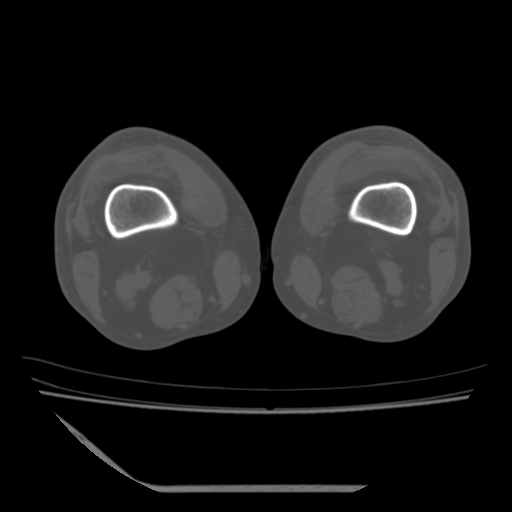

标题: CT13225:老年男性,左膝关节疼痛数月;请各位老师讨论。 [打印本页]

标题: CT13225:老年男性,左膝关节疼痛数月;请各位老师讨论。

骨质增生,骨性关节面硬化,关节积液,考虑退行性骨关节病

关节腔内少量积液,关节面退变。

双膝退变

骨质增生,骨性关节面硬化,关节间隙失常,关节积液,考虑退行性骨关节病.

这个病例诊断:退行性骨关节炎